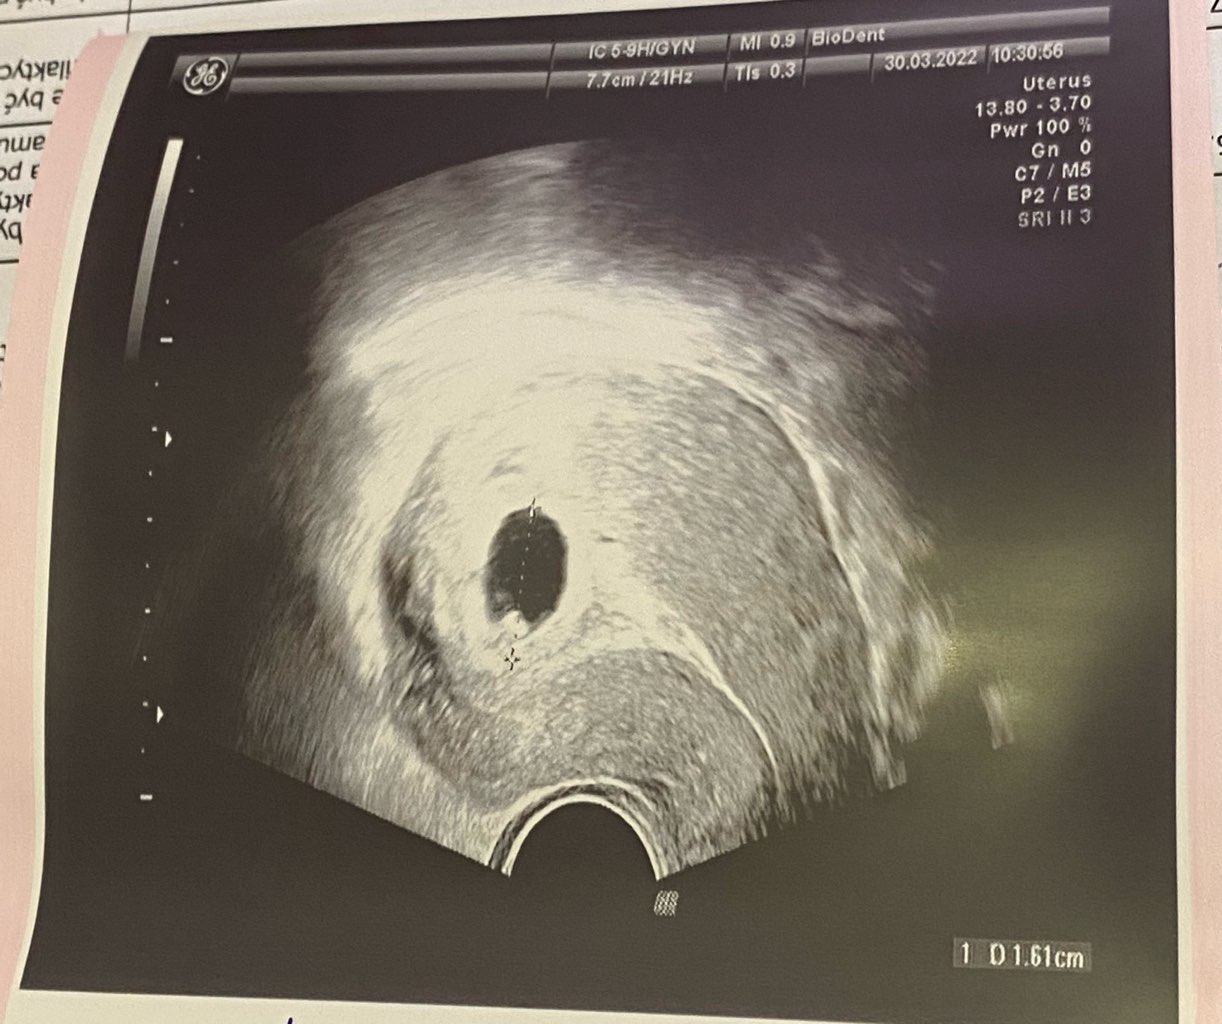

jeśli chodzi o ciąże bliźniacze to ja miałam pierwsze usg 23 marca(zdj z dwoma pęcherzykami) tydz później, bo wariowałam na sama myśl o bliźniakach poszłam na NFZ do ginekologa zrobić usg i był jeden pęcherzyk. Także mam nadzieje ze jest jedno 🙈🤣

• IMG_0267.jpg

IMG_0267.jpg

161 KB · Wyświetleń: 101